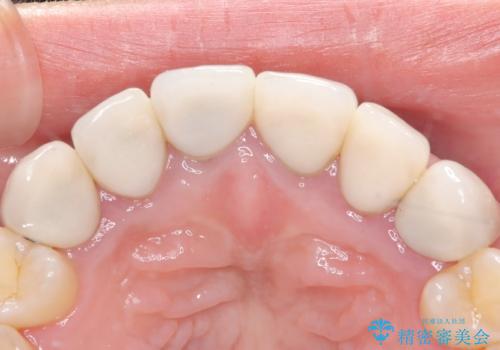

今回の治療では、まず原因となっていた前歯を慎重に抜歯し、その直後にインプラントを埋入しました。抜歯即時埋入は、歯を失うのとほぼ同時に新しい歯の土台を確保できるため、骨の吸収を防ぎ、仕上がりの美しさを保つ上で非常に有効です。また、治療当日に仮歯を装着することで、歯がない期間をなくし、患者様の精神的なご負担にも配慮しました。最終的に、周囲の歯と調和したオーダーメイドのセラミッククラウンを装着。機能性だけでなく、天然歯と見分けがつかないほどの自然で美しい前歯を取り戻していただけました。